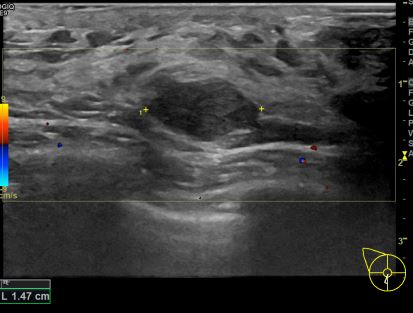

상기환자 외부검사상 이상소견으로 내원하신 30대여성으로 우측에 의심스러운혹 조직검사시행해 유방암 진단되었습니다.